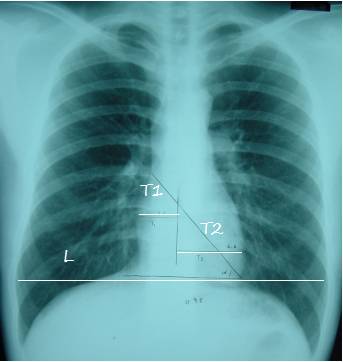

5.心影位置及大小

T1:心脏最右缘至前正中线距离

T2: 心脏最左缘至前正中线距离

L:通过膈肌顶部至两侧胸廓内沿并平行于膈肌的线

心胸比=(T1 T2)/L

1.正常<=0.50

2. 轻度增大 0.51-0.55

3. 中度增大0.56-0.60

4. 重度增大>=0.60